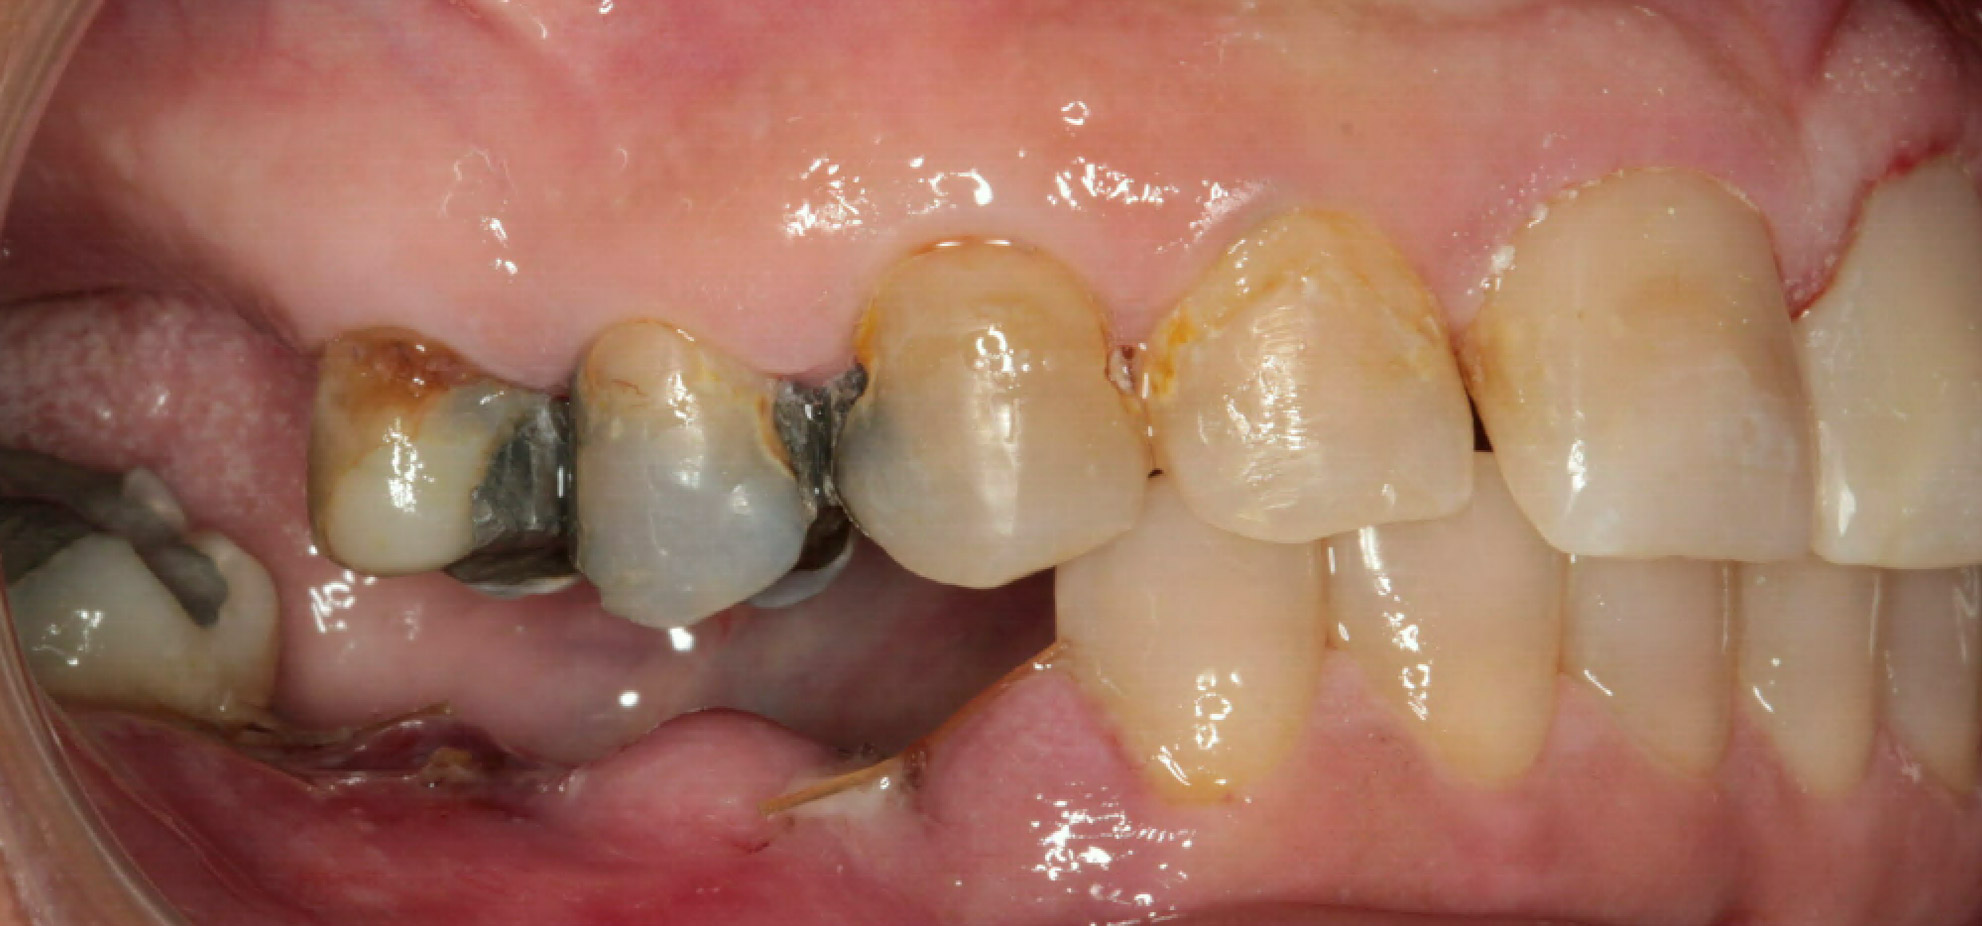

Intra Oral Pictures (3)

(Treatment in progress)

Intra Oral Pictures (4)